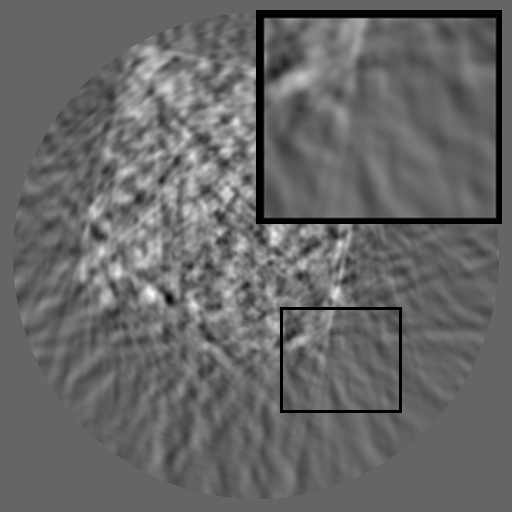

Refer to caption

(a) Mask

(b) SinoTx

(c) DiffIR

(d) HiDiffusion

(e) RePaint

(f) HRSino

(g) Ground Truth

Figure 3: Qualitative completion results on TomoBank (lines 1 to 2) and LoDoPaB (lines 3 to 4) with random mask (ratio = 0.8) at 1024×\times1024 resolution. Odd columns and even columns show the sinograms and reconstructed images, respectively.

4.2.3 Completion Quality

Tab 2 summarizes accuracy results. At 2048×\times2048 resolution, HRSino achieves the best performance among all baselines while remaining memory-efficient, demonstrating its ability to extend high-quality completion to resolutions where other diffusion models fail. At 1024×\times1024, HRSino delivers accuracy comparable to its computation-intensive counterpart RePaint, showing that our optimizations do not compromise fidelity at moderate scales. Compared to DiffIR, MCG, TD-Paint, and HiDiffusion, HRSino consistently achieves higher SSIM and PSNR across mask ratios, with improvements up to +0.03 SSIM and +1.8 dB PSNR. Fig 3 visualizes sinogram completion and reconstructed images, where HRSino produces nearly indistinguishable results from RePaint. These findings confirm that HRSino fundamentally extends diffusion-based completion to 2048×\times2048 resolution in a more memory- and runtime-efficient manner.